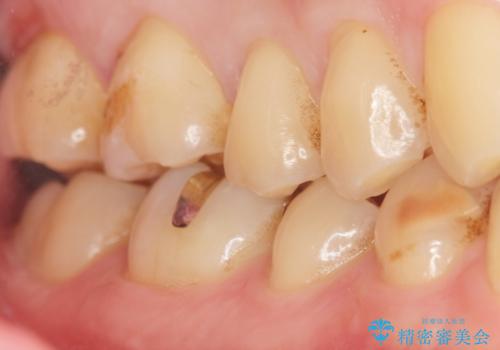

- 奥歯に食べ物がはさまることを主訴に来院された患者様です。

精査したところ、神経近くに及ぶ大きなう蝕を認めました。

神経をとらずに済むよう丁寧にう蝕を除去したのち、セラミックインレーで修復しました。